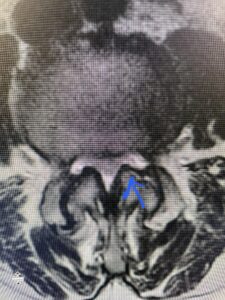

Another patient is a 62 year-old female with progressive low back pain and right leg pain and numbness that radiates to the top of her foot. She tried physical therapy and epidural injections. MRI demonstrated severe L3-4 stenosis and a grade 1 spondylolisthesis (Fig 4). There was L5-S1 and L4-5 disc collapse with modic end-plate changes. Biomechanically because of the significant degeneration of these disc spaces which stiffened the L4-S1 segment more stress was placed on the L3-4 segment, resulting in significant premature degeneration and compensatory stenosis and segmental instability. The MRI also showed pathologically, because of the slip, the L3 inferior processes were more anteriorly oriented and hence contributing to the majority of the lumbar canal compromise. Note the more sagittally-oriented facets in this case compared to the prior case (Fig 5). The patient underwent a decompressive laminectomy with attention of removing the inferior processes of L3 to fully decompress the canal. We also performed an L3-4 fusion with instrumentation (Fig 6). The patient had an uneventful postoperative course with improvement of leg pain. Of note with relief of the disabling leg pain patients are generally very happy. Patients can often manage their low back pain; it is the leg pain that they just can’t tolerate.

Fig 4: Sagittal T2-weighted lumbar MRI demonstrating L3-4 grade 1 spondylolisthesis with severe stenosis (blue arrow)

Fig 5 Axial T2-weighted lumbar MRI demonstrating significant L3 inferior facet contribution of severe stenosis (blue arrow)